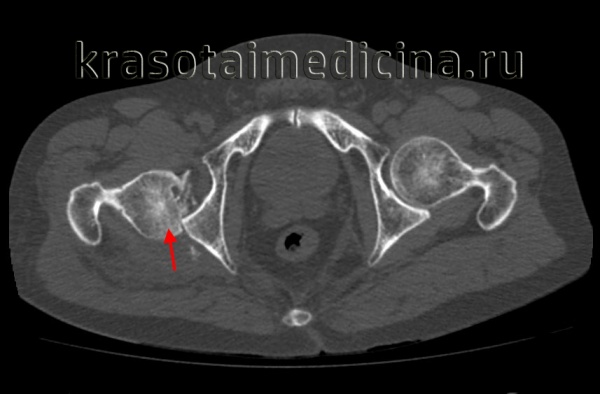

(Слева) КТ в передне-задней проекции, объемная 3D реконструкция: определяется задний вывих головки бедренной кости. КТ выполняется перед закрытой репозицией только если она оказалась неудачной. КТ позволяет оценить положение смещенных осколков, препятствующих репозиции.

(Слева) КТ, аксиальный срез: в данном вывихе, репозиция которого возможна только под общей анестезией, визуализируется головка бедренной кости, вколоченная в заднюю губу вертлужной впадины.